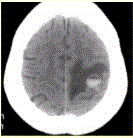

问题 患者女,55岁,右侧肢体无力3d。头颅CT显示如下图。 可能的诊断为(提示为进一步明确诊断,头颅CTA及CT灌注如下图(CBV未见血流量升高,CTA未见异常供血动脉)。)

选项 A.急性脑血肿 B.转移瘤伴出血 C.胶质瘤伴出血 D.少枝胶质细胞瘤伴出血 E.血液系统病变伴脑出血 F.脑脓肿 G.血管畸形伴出血

答案 ABE